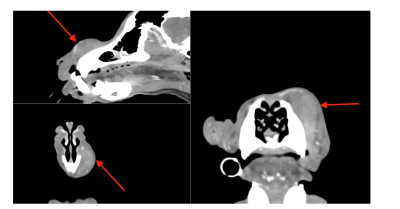

Niestety nasz spokój zakłócił ostatnio pyszczek Maksia - bo pojawiło się na nim jakaś opuchlizna, ale przy dotykaniu jest twarde. Nie ma żadnych innych objawów, a miejsce to nie sprawia mu bólu. Aktualnie jesteśmy już po wizytach u specjalistów - i tutaj sprawa wygląda dosyć źle i poważnie, ponieważ podejrzewany jest nowotwór - kostniakomięsak, z racji, że jest to duży pies i to jest podobno typowy rak dla tej rasy. Nie mamy jednak tego jeszcze potwierdzonego w badaniach. Są to jednak przypuszczenia weterynarza onkologa.

Na wizytach nie było możliwości zrobienia badań, bo pobranie biopsji jest niemożliwe ze względu na twardość tego miejsca, a normalne rtg jest zbyt ograniczone, żeby można było to dobrze obejrzeć.

Mamy skierowanie na tomografię głowy, szyi i klatki piersiowej - do tego biopsja zmiany rozrostowej w znieczuleniu podczas tomografii.

Maxiu jest po pełnej diagnostyce.

Zmiana okazała się włókniakomięsakiem :cry:

Aktualnie nie tracimy czasu i Maks przyjmuje chemię metronomiczną. Do tego rozważamy operację, którą zalecił chirurg onkolog Anna Rajska Krysa z przychodni Bemowo Wet - tam robiliśmy wszystkie badania i tam są w miarę dostępne terminy jesli chodzi o wizyty, dlatego zdecydowaliśmy się na leczenie w tym miejscu.

Obraz TK 1.jpg

Plik ściągnięto 6 raz(y) 29.5 KB

Obraz TK 2.PNG

Plik ściągnięto 7 raz(y) 344.31 KB